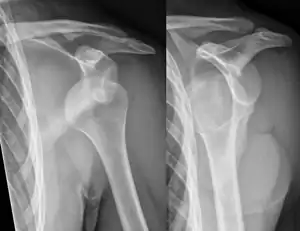

A diagnosis of shoulder dislocation is often suspected based on the person's history and physical examination. Radiographs are made to confirm the diagnosis. Most dislocations are apparent on radiographs showing incongruence of the glenohumeral joint. Posterior dislocations may be hard to detect on standard AP radiographs, but are more readily detected on other views. After reduction, radiographs are usually repeated to confirm successful reduction and to detect bone damage. After repeated shoulder dislocations, an MRI scan may be used to assess soft tissue damage. In regards to recurrent dislocations, the apprehension test (anterior instability) and sulcus sign (inferior instability) are useful methods for determining predisposition to future dislocation.

In over 95% of shoulder dislocations, the humerus is displaced anteriorly.[7] In most of those, the head of the humerus comes to rest under the coracoid process, referred to as sub-coracoid dislocation. Sub-glenoid, subclavicular, and, very rarely, intrathoracic or retroperitoneal dislocations may also occur.[8]

A Hill–Sachs lesion is an impaction of the head of the humerus left by the glenoid rim during dislocation.[6] Hill-Sachs deformities occur in 35–40% of anterior dislocations. They can be seen on a front-facing X-ray when the arm is in internal rotation.[9] Bankart lesions are disruptions of the glenoid labrum with or without an avulsion of bone fragment.

Anterior dislocation of the right shoulder. AP X ray

Anterior dislocation of the right shoulder. Y view X ray.